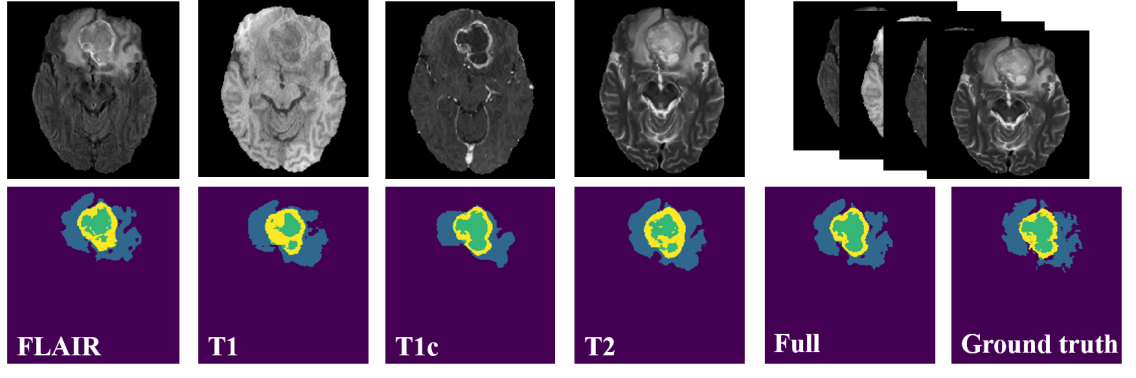

Segmentation and associated volume quantification of heterogeneous histological sub-regions are of great value to the diagnosis/prognosis, therapy planning, and follow-up of brain tumors (Bakas et al. 2018). Multi-parametric magnetic resonance imaging (MRI) is the current standard of care for clinical imaging diagnosis of brain tumors (Iv et al. 2018). Specifically, four MRI modalities (in this work, we refer to MRI sequences as modalities) are commonly used to provide complementary information and support sub-region analysis: T1-weighted (T1), contrast enhanced T1-weighted (T1c), T2-weighted (T2), and T2 fluid attenuation inversion recovery (FLAIR), where the first two highlight tumor core and the last two highlight peritumoral edema (Figs. 1(a) and (b)). In recent years, deep learning methods have greatly advanced the state of the art of brain tumor segmentation with multimodal MRI (Chen et al. 2020; Chen, Ding, and Liu 2019; Ding et al. 2020; Myronenko 2018; Zhou et al. 2020). However, these methods were optimized for the ideal scenario where the full set of all modalities are present. While in practice, scenarios of missing one or more modalities commonly occur due to image corruption, artifacts, acquisition protocols, allergy to contrast agents, or simply cost.

Refer to caption

Figure 4: Example segmentation results of the proposed M3AE framework on BraTS 2018 using four individual modalities and all of them. Blue: edema; yellow: enhancing tumor; and green: necrotic and non-enhancing tumor core.

As we can see, the proposed M3AE yields the strongest performance for all the three evaluated tumor regions and on both datasets, with the highest mean DSCs averaged over all modal combinations. It is worth mentioning that as a catch-all method, our M3AE substantially outperforms the two dedicated methods (ACN and SMU-Net), while using only a single trained model. In contrast, the latter two require 15 models for all the modal combinations. This makes M3AE more efficient to both train and deploy in practice, in addition to being superior in performance. We conjecture that two important facts play key roles here: (1) the co-training strategies employed in the dedicated methods only modelled the one-to-one correlation between the full modalities and each missing-modal situation, whereas our self distillation implicitly models the versatile correlations between all heterogeneous missing-modal situations; and (2) the random modality dropout and patch masking in M3AE are likely to serve as effective data augmentation that helps model training, which is unavailable in paired co-training where the absent modalities are fixed. Meanwhile, our M3AE outperforms RFNet, too, which is the previous best performing method and also a catch-all method. Taking BraTS 2018 for example, compared with RFNet, the mean DSCs of M3AE are slightly higher in whole tumor (85.8% versus 85.5%), apparently higher in tumor core (77.4% versus 76.0%), and substantially higher in enhancing tumor (59.9% versus 56.6%). Besides, using a vanilla encoder-decoder architecture, our M3AE framework is also more memory-economic and computation-efficient to deploy than RFNet, which employed multiple encoders with substantially more parameters and GFLOPS (Fig. 1(c)). In conclusion, the M3AE framework sets a new SOTA for multimodal brain tumor segmentation with missing modalities, while at the same time using an efficient and economic architecture for deployment. Figure 4 shows example segmentation results by M3AE.